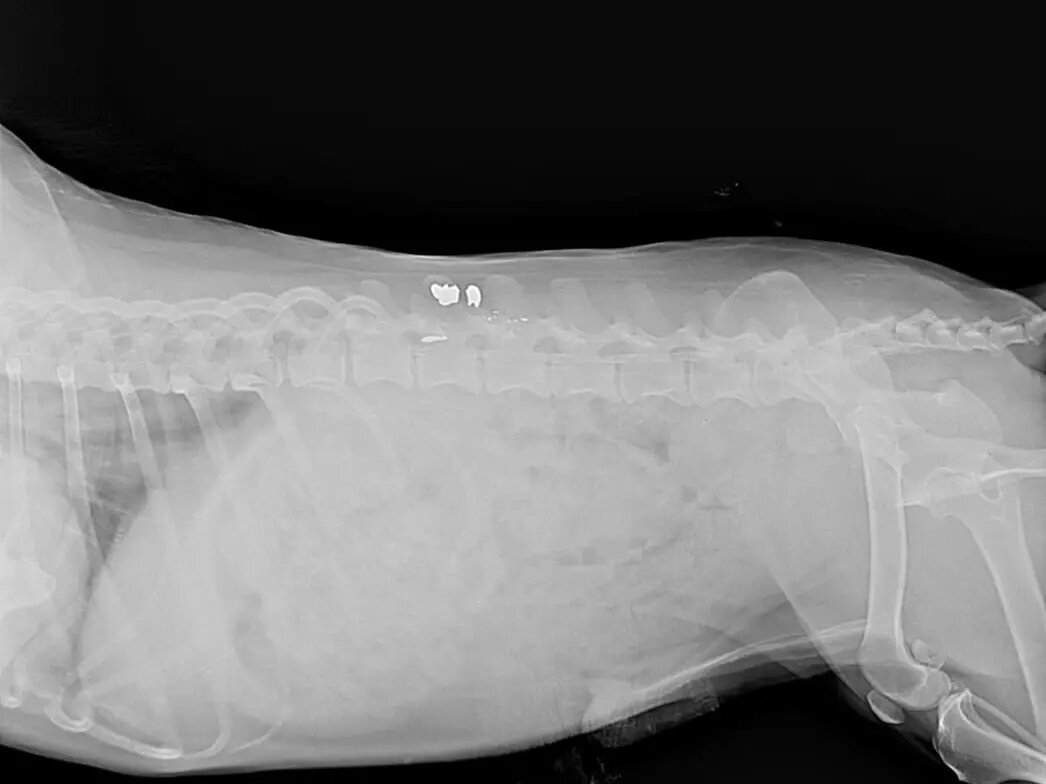

В приюте подумали, может, просто защемило нерв, и решили сделать рентген. На снимке обнаружилось невероятное. Все это время в теле животного была пуля.

Изначально все подумали, что именно из-за пули у песика парализовало лапы. Как уточнили в приюте, сейчас врач предполагает, что причина внезапного паралича не в пуле. За несколько лет нахождения в теле она капсулировалась. Из-за чего мигрировать и вызывать какие-то воспалительные процессы уже не может.

Что же произошло с Веней, до сих пор неясно. Понять, в чем проблема, поможет КТ.

- Необходимо посмотреть позвоночный столб, есть там разрыв или нет, - сказали врачи сотрудникам приюта.